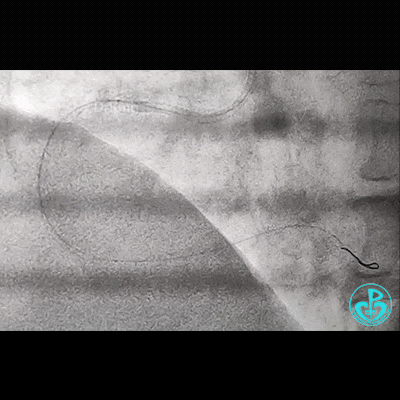

治疗过程

处理右冠,XB RCA,Sion、Sion blue导丝,2.0×20mm球囊。支架植入过程相当顺利,很快就完成,窃喜!心想后扩后马上结束!